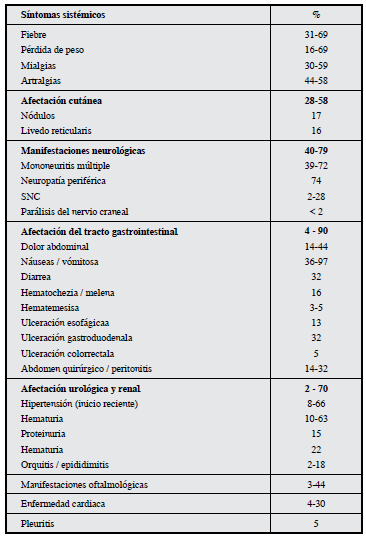

La sintomatología es muy heterogénea, debido a que la inflamación arterial puede afectar a un solo órgano o incluso, en casos más severos conducir a un fracaso multiorgánico fulminante comprometiendo así varios sistemas, y generando una amplia constelación de manifestaciones clínicas; que dependerán principalmente del número y localización de las arterias afectadas. La frecuencia de las manifestaciones clínicas de la poliarteritis nodosa se describen en laTabla 1 5,6.

El diagnóstico se apoya en los criterios establecidos en 1990 por el consenso de Chapel Hill y el Colegio Americano de Reumatología (CAR), los cuales sólo han sido validados en adultos (Tabla 2) 7. La presencia de tres criterios o más tiene una sensibilidad de 82.2% y una especificidad de 86.6% 7-9.